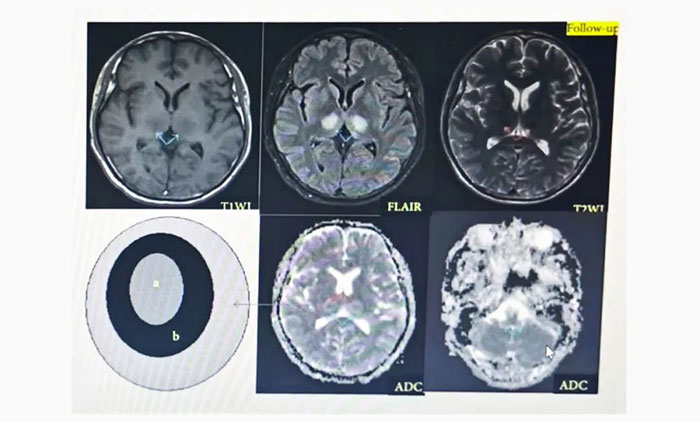

女子反應(yīng)遲鈍,如電腦“宕機(jī)”,原來是患罕見性腦病,張靜波團(tuán)隊聯(lián)手診治帶來希望

神經(jīng)內(nèi)科7A病區(qū)張靜波主任介紹,ANE發(fā)病機(jī)制并不十分清楚,國際上比較公認(rèn)的是細(xì)胞因子增高導(dǎo)致大腦繼發(fā)性損害,若能積極控制細(xì)胞因子水平,將有望改善預(yù)后,關(guān)鍵在于在神經(jīng)系統(tǒng)損壞不可逆之前,及時發(fā)現(xiàn)...【詳細(xì)】